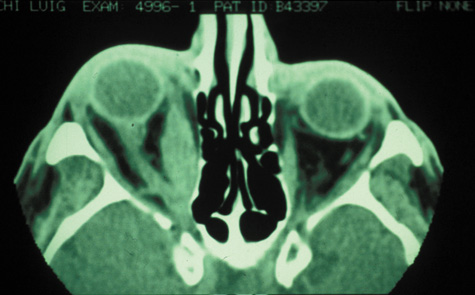

Routine skull films and polytomography have been supplanted by CT in the evaluation of patients with orbital cellulitis.57 CT allows the clinician to differentiate a preseptal cellulitis from an orbital cellulitis.58 If orbital cellulitis has resulted from adjacent intercurrent sinus infection, the diagnosis can be made and the extent of the sinus disease estimated. Sinuses may show changes of osteomyelitis with blurring of the osseous margins of the sinuses, air–fluid levels, or inflammatory tissue within the normally aerated sinus.59 Central nervous system complications can be assessed by neuroimaging, and progression of disease can also be monitored.58

CT should be performed using thin-section (2–4 mm) high-resolution scanning with multiple views of both bone and soft tissue detail.53 Axial and coronal views should be obtained; in one-third of patients with subperiosteal abscesses, the abscess was seen in the coronal sections only.18 Helical CT is a fairly new technology that allows increased resolution with decreased imaging time.60 This type of scan may be especially beneficial in children because of the ability to obtain good imaging with a shorter imaging time.60 elica He HhIntravenous contrast material is not advocated at all centers because there is intrinsically high contrast between infectious changes and orbital fat. However, some authors believe that it is essential to the diagnosis, and it thus remains the preference of the individual clinician, as well as the neuroradiologist.22,59,62

With preseptal inflammation, CT demonstrates soft tissue swelling of the eyelids and tissue adjacent to the orbital septum (Fig. 15). The orbit is not involved, and usually the sinuses do not show evidence of inflammation. The distinction between inflammatory preseptal cellulitis and edema cannot be made.63

Fig. 15. Computed tomography showing preseptal cellulitis of left eye. Note that all swelling is anterior to the orbital septum.